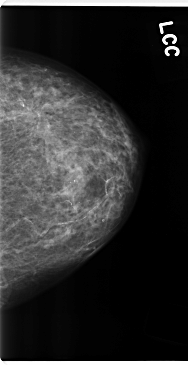

C_0184_1.LEFT_CC

LEFT_CC LINES 4744 PIXELS_PER_LINE 2432 BITS_PER_PIXEL 12 RESOLUTION 50 NON_OVERLAY